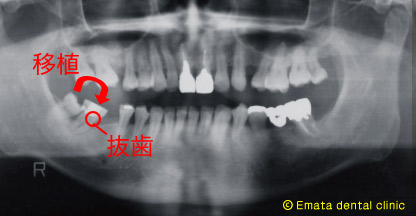

本日のインプラントのオペは、歯牙移植したあとに、その隙間にインプラント治療を埋入したオペでした。ちょっとわかりずらいですね。

患者さんは下顎の奥歯が歯が傾斜して歯周病も進み、残念ですが歯は抜歯の適応です。患者さんは親知らずを何とか移植につかえないかという強い希望がありました。

移植をおこないその移植歯を簡単な矯正(アップライト)し、今日移植歯と自分の歯の間にインプラント治療を行いました。

親知らずを移植歯につかいました。 |